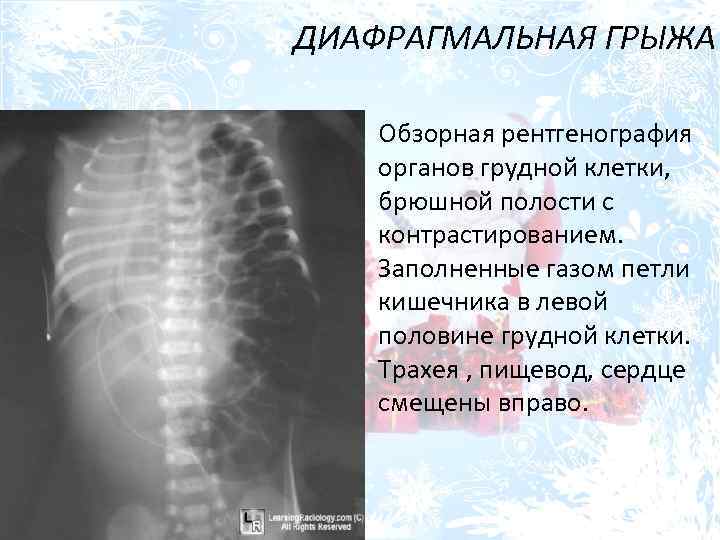

Нормы обзорной рентгенографии брюшной полости